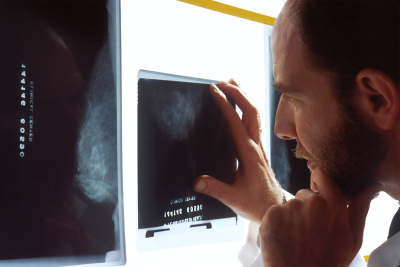

Εξέταση αίματος ανιχνεύει 50 διαφορετικούς τύπους καρκίνου, σύμφωνα με τον NHS

Νέα εξέταση αίματος «προβλέπει» τον καρκίνο ένα χρόνο πριν καν σχηματιστεί